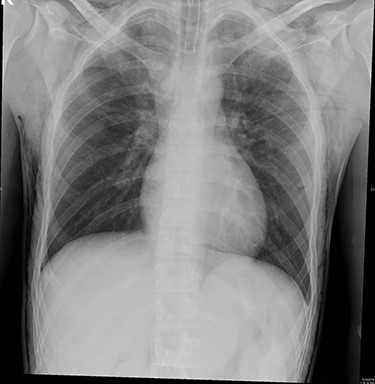

The surgeon was informed about the hypercarbia and desufflation. When examining the patient, the subcutaneous crepitus was found to be reaching up to the neck. Arterial blood gas confirmed respiratory acidosis (pH, 7.23; PaCO2, 56.1 mmHg; HCO3, 23.2 mmol/l; PaO2, 524 mmHg). About 15 min later, the CO2 level started decreasing until it reached 45 mmHg. Approximately 4 hours since the start, the operation was completed, and the patient was fully awake with stable vitals and the CO2 level below 45. Bedside lung ultrasound was immediately performed to exclude pneumothorax. Chest radiography was performed before extubating the patient, and bilateral surgical emphysema in the subcutaneous tissues of the chest and root of the neck was noted. Pneumothorax and pneumomediastinum were excluded (Fig. 1).

Bilateral surgical emphysema at subcutaneous tissues of the chest and root of the neck was found.